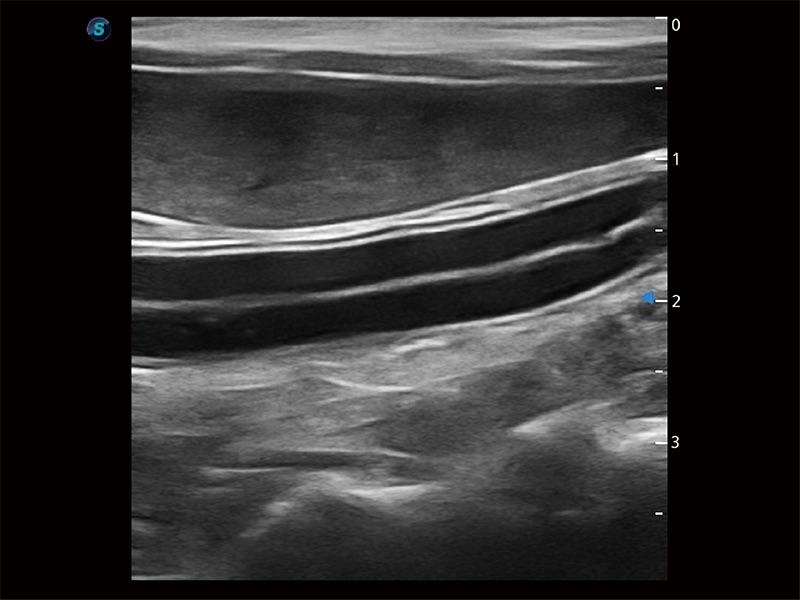

為精細(xì)結(jié)構(gòu)及組織邊緣提供高清晰度的圖像和更大的成像視野。幫助減輕醫(yī)生的用眼疲勞,快速精準(zhǔn)獲得測量的數(shù)據(jù)。

ProPet 80 全新的動物超聲智能軟件和豐富的探頭群,為動物醫(yī)生提供了高清晰度和精細(xì)分辨率的圖像,無論在寵物、馬科、畜牧還是實(shí)驗(yàn)室動物等應(yīng)用中都可以輕松應(yīng)對,為您的日常工作帶來滿意的體驗(yàn)。